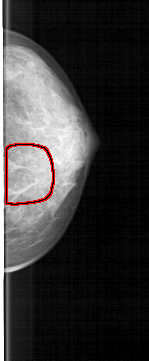

D_4130_1.LEFT_CC

LEFT_CC LINES 4681 PIXELS_PER_LINE 1936 BITS_PER_PIXEL 12 RESOLUTION 43.5 OVERLAY

FILE: D_4130_1.LEFT_CC.OVERLAY

TOTAL_ABNORMALITIES 1

ABNORMALITY 1

LESION_TYPE CALCIFICATION TYPE FINE_LINEAR_BRANCHING DISTRIBUTION LINEAR

ASSESSMENT 3

SUBTLETY 3

PATHOLOGY MALIGNANT

TOTAL_OUTLINES 1

BOUNDARY